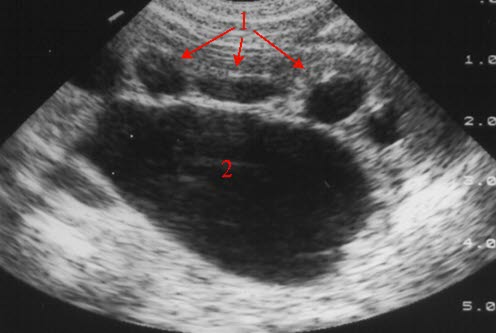

Overgangs-stenose

Overgangs-stenose (UL)

Kraftig utvidelse av calyces (1) og ekstrarenalt nyrebekken (2)